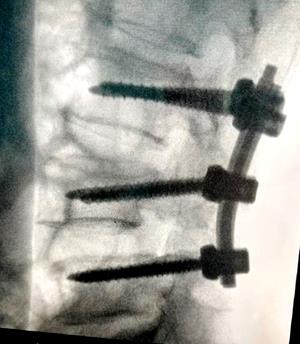

患者经腰1椎体经皮椎体成形术+腰4椎体切开复位钉棒系统内固定术后腰椎部位放射影像

切开复位钉棒系统内固定术(正、侧位)放射影像(传统开放式手术)